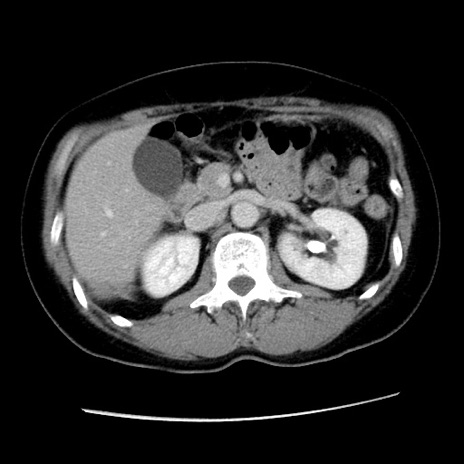

症例10(横断像)

【症例】 50歳代女性

【主訴】 腹痛

【現病歴】前日生レバーを食べた。今朝に排便あり。 昼前に突然発症の腹痛を生じ、当院救急外来を受診した。

【既往歴】 子宮筋腫にてで子宮全摘後

【身体所見】 意識清明、腹部:平坦、軟、下腹部やや左を中心に圧痛・反跳痛あり、筋性防御あり

【データ】WBC 7800、CRP 0.07